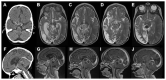

A dysregulated host immune response significantly contributes to morbidity and mortality in tuberculous meningitis (TBM). Effective host directed therapies (HDTs) are critical to improve survival and clinical outcomes. Currently only one HDT, dexamethasone, is proven to improve mortality. However, there is no evidence dexamethasone reduces morbidity, how it reduces mortality is uncertain, and it has no proven benefit in HIV co-infected individuals. Further research on these aspects of its use, as well as alternative HDTs such as aspirin, thalidomide and other immunomodulatory drugs is needed. Based on new knowledge from pathogenesis studies, repurposed therapeutics which act upon small molecule drug targets may also have a role in TBM. Here we review existing literature investigating HDTs in TBM, and propose new rationale for the use of novel and repurposed drugs. We also discuss host variable responses and evidence to support a personalised approach to HDTs in TBM.